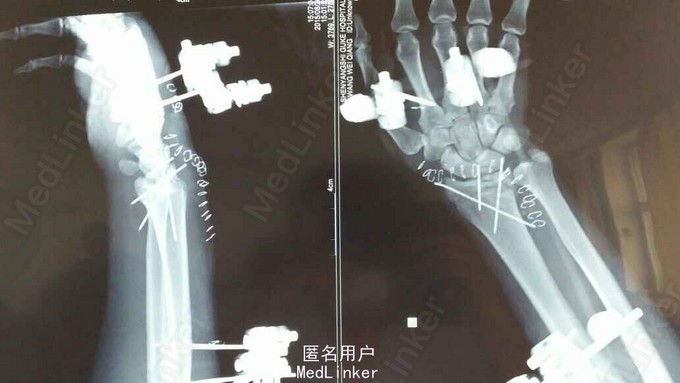

诊断:双尺桡骨远端粉碎性骨折 治疗:入院后,给予手法复位夹板固定,左手神经症状明显缓解,给予对症治疗,消肿后,于2015年8月27日行手术治疗。

请问大家,对于这种骨折是行外架+克氏针固定好,还是钢板固定好?